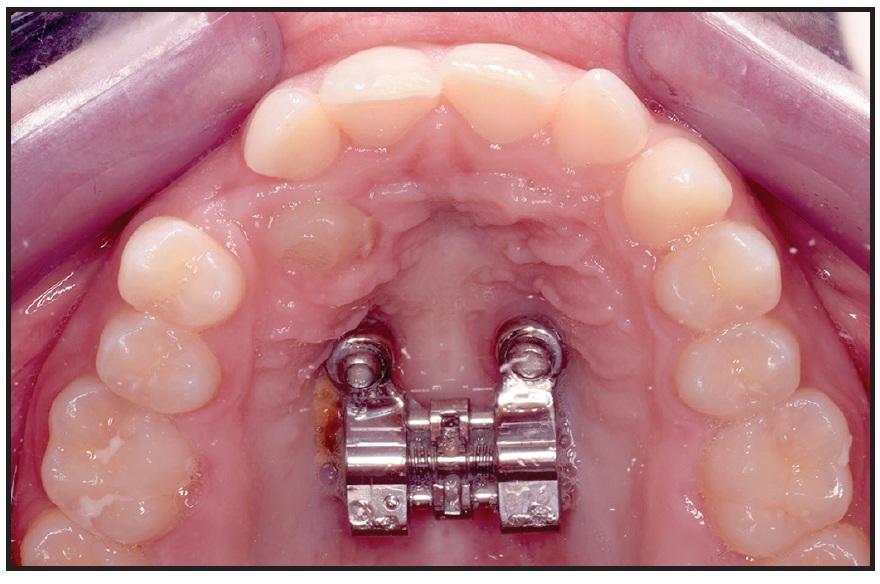

After local anesthesia (2% lidocaine) was administered in the surgical sites, the surgical guide was fitted to the occlusal surfaces of the posterior teeth. Two OrthoEasy Pal** miniscrews were inserted into the adapted pickup driver and mounted on a contra-angle handpiece at a low speed of 40rpm (Fig. 8). The cylindrical guide tubes were designed according to the dimensions of the pickup driver to ensure that the screws were inserted at the correct angle and the planned depth (Fig. 9).

Fig. 9 Two parallel miniscrews after insertion in anterior palate.